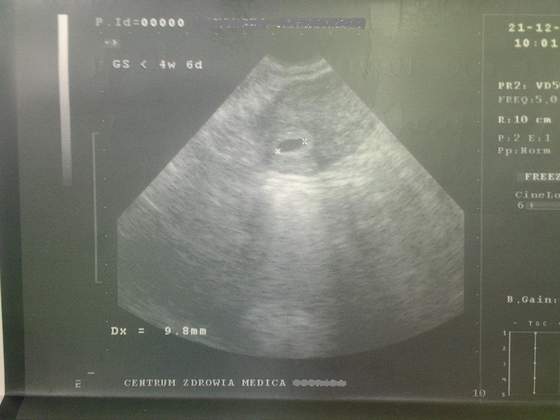

u mnie dopiero początek , moja ginka na 1 usg (21 grudnia) powiedziała, że jest mniej niż 4 tyg i 6 dni, było widać tylko centymetrowy pęcherzyk, dziwi mnie że nie zapytała czy biorę kwas foliowy itp, po prostu nic. Wy dokładnie wiecie który dzień macie hmmmm czemu mi nie powiedziała??? to się określa z wielkości fasolki?

No ale 1 cm. pęcherzyk odpowiada mniej wicej 5 tygodniowi,hmmm...

GS (Gestational Sac) - wymiar pęcherzyka ciążowego

HBD-GS(cm) (czyli zaleznosc miedzy wiekiem ciazy wyrazonym

w tygodniach a wielkoscia pecherzyka w cm)

5.0 tydz 1.0 cm (10 mm)